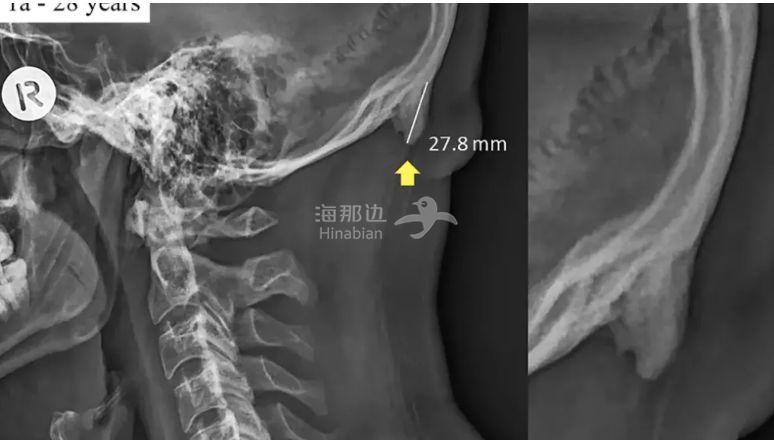

这个惊人的现象是澳洲阳光海岸大学发现的,这所大学的研究人员通过对1000多张18岁只36岁人群头骨X光进行分析,收关得出了一个结论,如下图所示,人类的后脑,会出现一块变异的骨刺!

而枕外隆突的大小不尽相同,上图中骨刺突出的数据为27.8mm,这个数值属于异变程度较高的。

平均数值大概在24.5mm左右。